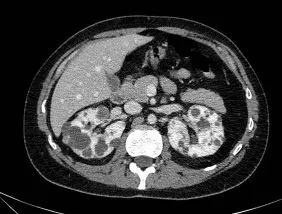

Doação renal em mulheres jovens pode impactar mais o feto do que a mãe — e esse dado muda o pré-operatório. O maior estudo já feito mostra aumento de PIG e sinais de disfunção placentária silenciosa, especialmente em nulíparas. Se você ainda não discute isso de forma explícita no consentimento, talvez esteja subestimando o risco.